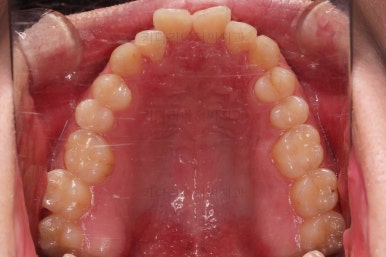

초진 시 입안의 모습입니다.

교합이 많이 안좋습니다.

위아랫니가 서로 엇갈려 가며 지그재그로 껴 들어가야 어금니 맞물림이 생기는데요.

이번 환자분은 아랫니, 아래턱이 전반적으로 앞으로 나와 있어서 교합이 전혀 안되고 있는 상태였습니다.